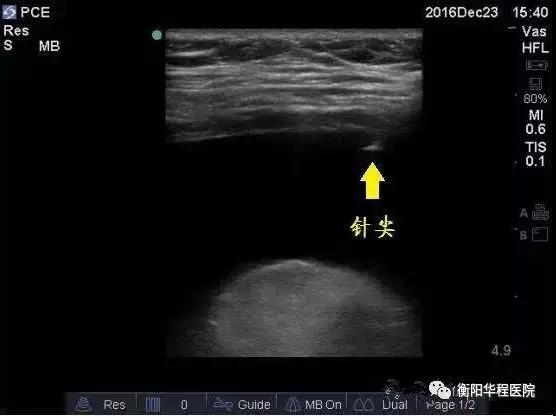

立即使用 20 G 留置針行實(shí)時(shí)超聲引導(dǎo)下心包穿刺術(shù),從準(zhǔn)備物品到抽到心包積液,用時(shí) < 5分鐘。

圖3 采用平面內(nèi)超聲引導(dǎo)技術(shù)可實(shí)時(shí)觀察到針尖位置

圖4 使用20G留置針穿刺抽液損傷較小、使用方便,適用于胸壁較薄患者術(shù)畢。